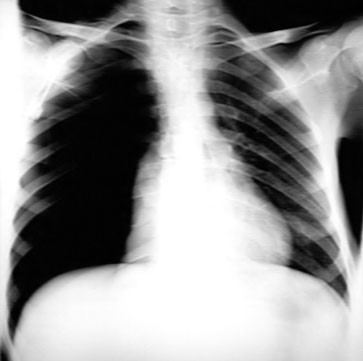

En el diagnóstico del neumotórax, la radiografía de tórax es una herramienta fundamental que permite observar características específicas asociadas con la acumulación de aire en el espacio pleural. En una radiografía de tórax, la presencia de un neumotórax se manifiesta como un área de radiolucidez, o «luz», entre la pared torácica y el pulmón, donde no se aprecian las marcas pulmonares normales. Esto indica la existencia de aire en el espacio pleural. Además, la visualización de una «línea pleural», que es la línea delgada formada por la pleura visceral separada de la pleura parietal por el aire, es un hallazgo diagnósticamente significativo.

En algunos casos, los pacientes con neumotórax pueden desarrollar un derrame pleural secundario, que puede ser identificado en la radiografía de tórax como un nivel característico de aire-fluido. Esto se presenta como una interfaz entre el aire y el líquido en el espacio pleural, evidenciada en la radiografía.

Para los pacientes que se encuentran en posición supina, la radiografía de tórax convencional puede no mostrar claramente el neumotórax, y en su lugar, se puede observar un «surco profundo» en el área costofrénica. Este hallazgo radiológico se debe a la acumulación de aire en el espacio pleural, que desplaza el diafragma hacia arriba, creando una radiolucidez anormal en la región costofrénica.

En situaciones de neumotórax de tensión, la radiografía de tórax revela una acumulación significativa de aire en el hemitórax afectado. Este exceso de aire provoca un desplazamiento del mediastino hacia el lado opuesto, una característica clave para la identificación de esta condición crítica.

En un paciente joven que presenta síntomas típicos de neumotórax espontáneo primario, el diagnóstico suele ser bastante evidente y puede confirmarse fácilmente mediante una radiografía de tórax (CXR). Este tipo de neumotórax generalmente ocurre en personas jóvenes, delgadas y saludables, y se manifiesta con síntomas como dolor torácico agudo y disnea. En estos casos, los hallazgos en la CXR muestran típicamente una área de radiolucidez entre la pared torácica y el pulmón, junto con una línea pleural visible, que son características diagnósticas de la presencia de aire en el espacio pleural.